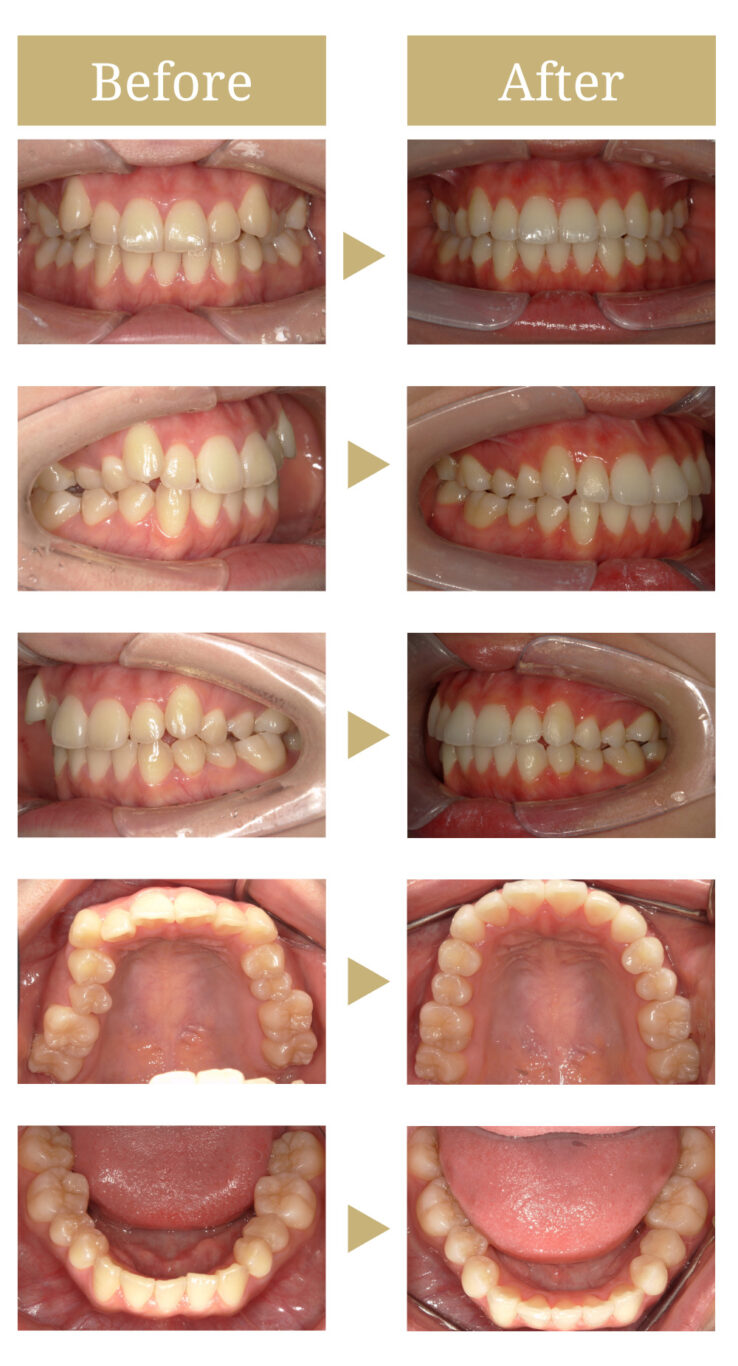

前歯の八重歯に対するインビザライン矯正治療

歯が並ぶスペースが不足していることで歯列の叢生(でこぼこ)が生じていました。

マウスピース矯正と並行してホームホワイトニングをすることでさらに審美性が向上できることをお伝えし一緒に行いました。

マウスピース矯正34枚のプランで治療を始めました。

適宜歯間調整処置を行い歯列を整えていきました。

途中ホームホワイトニングを1か月半ほど行いました。

歯列の叢生がなくなり、清掃性も向上し将来的な歯周病・虫歯のリスクも軽減させることができました。

また、噛み合わせのバランスが良くなったことで奥歯への余分な負荷を減らすことができています。

治療前の状態

全体的なセルフケアの状態は安定していましたが、前歯のねじれにより着色が付きやすいところがありました。

また、前歯の非接触部位が多いため奥歯に嚙み合わせの負荷がかかりやすい状態でした。

治療後の状態

歯列の叢生がなくなり、清掃性も向上し将来的な歯周病・虫歯のリスクも軽減させることができました。

また、噛み合わせのバランスが良くなったことで奥歯への余分な負荷を減らすことができています。

またホームホワイトニングを併用したことで歯の色も白くなり、患者様も口元に自信が持てるようになったと言っていただけました。